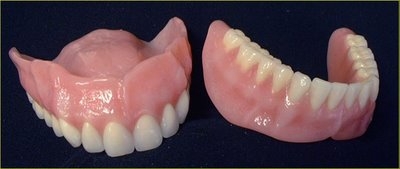

Các loại hàm tháo lắp

Giải pháp nào cho mất răng toàn bộ?

Hàm giả tháo lắp

Khi mất một hay nhiều răng vĩnh viễn mà chúng ta không phục hồi lại những răng đó...

Hàm giả và những thắc mắc thường gặp

Hàm giả được gọi là hàm giả thông thường hay hàm giả lắp liền tùy thuộc...